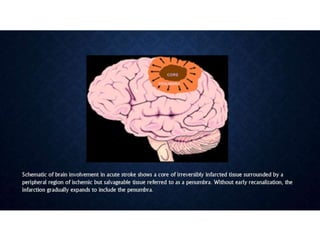

• • Is there a “core” of critically ischemic infarcted tissue, and if so, how

large?

• • Is there a “penumbra” of severely ischemic but potentially viable

tissue?

• III. to identify critically ischemic or irreversibly infarcted tissue (“core”)

and to identify severely ischemic but potentially salvageable tissue

(“penumbra”).

• This information can guide triage and management in acute stroke.